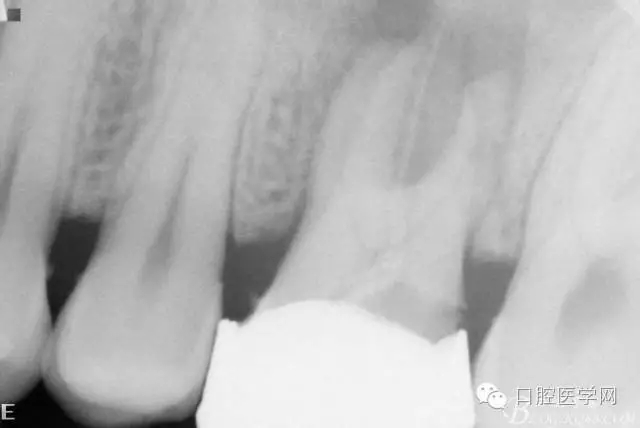

檢查26Ⅲ°松動(頰舌向、近遠中向、頜齦向)。X線片顯示根尖周彌漫性炎性陰影。

初診X線片